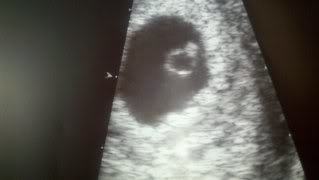

What does this US finding indicate?

Early 1st trimester

(Diamond ring sign)

Implanted in uterine wall

(Trophoblast + inner cell mass; would show diamond ring sign on US)